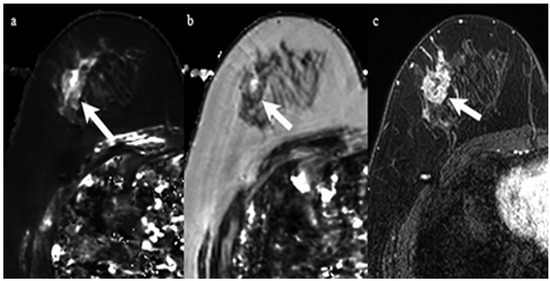

3.2. Relationship with ER Status

Clinical and pathological characteristics, and quantitative MRI values for the 29 lesions are shown in Table 1. No statistical significance was found between the ER-positive cancers and the ER-negative cancers regarding age and tumor diameter. The Ki-67 of ER-negative cancers was significantly higher than that of ER-positive cancers (p < 0.05). Mean T2 relaxation of ER-negative cancers (92.1 ± 13.0 msec) was significantly higher than that of ER-positive cancers (72.7 ± 15.7 msec, p = 0.01) (Figure 1, Figure 2 and Figure 3). Mean T1 relaxation and PD of ER-negative cancers were higher than those of ER-positive cancers, but no significant difference was observed between them. The AUCs of T1, T2, and PD for the differentiation of ER-negative cancers from ER-positive cancers were 0.74 (95% confidence interval (CI): 0.54–0.88), 0.87 (95% CI: 0.69–0.97), and 0.62 (95% CI: 0.42–0.79), respectively. The T2 value had the highest AUC, followed by T1 and PD. The optimal sensitivity and specificity of the T2 value were 100% and 78%.

Figure 2. A 59-year-old woman with invasive ductal carcinoma in the right breast. Immunohistochemical staining showed negativity for estrogen receptor and Ki-67 of 60%. (a) T1 map shows a high signal mass. Mean T1 of the mass was 1477 msec. (b) T2 map shows a high signal mass. Mean T2 of the mass was 96 msec. (c) Corresponding contrast enhanced MR image shows a mass with heterogeneous enhancement.